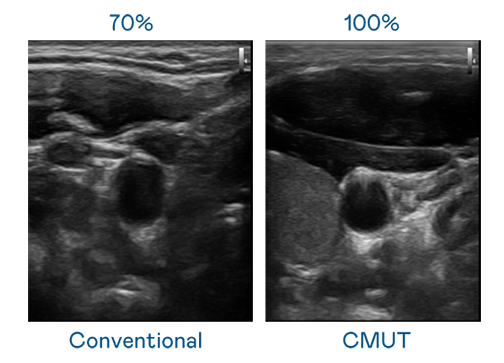

CMUT 技术是一种用电容式微机电元件来产生超音波讯号的技术。与传统 PZT 压电式技术相比,CMUT 频宽增加 30%,更宽频的超音波讯号让影像解析度大幅提升,是实现高影像品质医疗超音波扫描、促进精准医疗发展的关键技术。

超音波影像的解析度高低,首先取决于探头能发出的讯号频宽。朋友的闺蜜2线观高清电视 CMUT 可提供高清晰的超音波讯号,提供高频宽、高灵敏度、影像纹理细节更高的超音波影像,协助医护人员缩短影像判读时间及利用精准的医疗影像进行诊断。